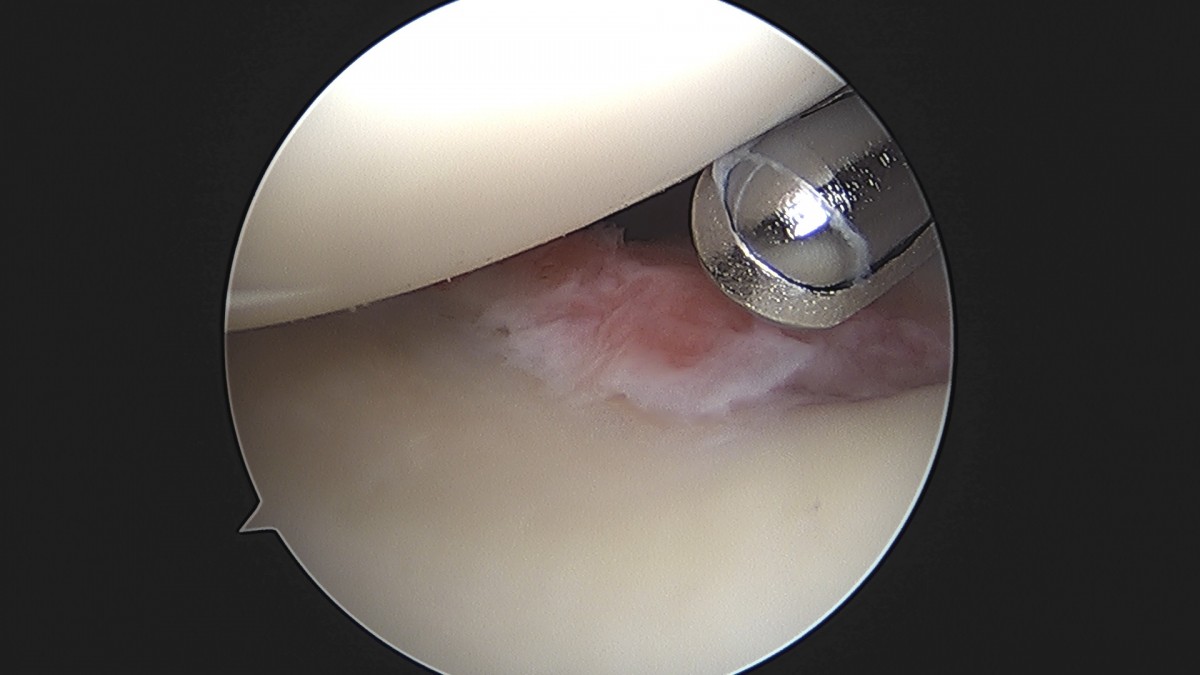

이재상원장님 어깨 견봉하 감압술 및 관절낭 이완술 주혜O 환자

dae765e4d9ac96aee867c9d6292d8784_1758003912_7954.jpg